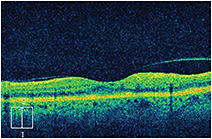

A 79-year old woman complained of decreased visual acuity – from 20/25 to 20/50 – of 5 weeks’ duration. A color fundus photograph of the left eye (Figure 1) showed macular edema and scattered intraretinal hemorrhages. Significant intraretinal dye leakage due to retinal angiomatous proliferation (RAP) was seen on the fluorescein angiogram (Figure 2). The OCT image (Figure 3) demonstrated intraretinal edema with insignificant vitreomacular adhesion. At follow-up, the patient received aflibercept 2 mg intravitreally and returned in 4 weeks for re-evaluation. Her visual acuity had improved to 20/30 and the repeat OCT image (Figure 4) showed complete resolution of the intraretinal edema.

Figure 4